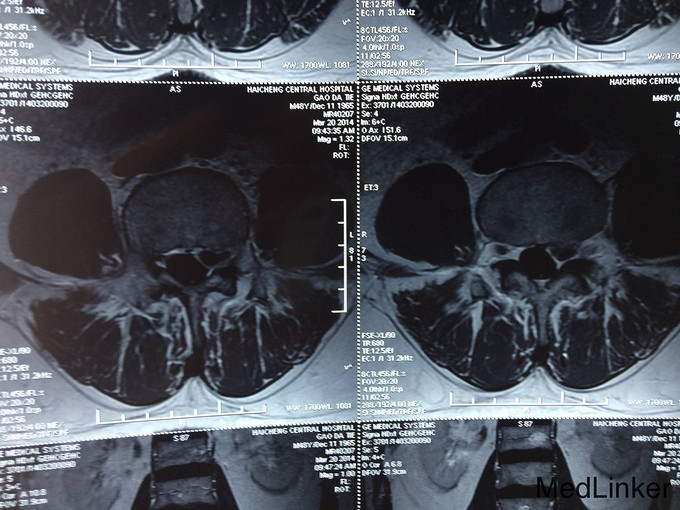

主诉:腰痛加重及左下肢疼痛1个月 现病史:患者自述腰痛10余年,休息及卧床缓解,不影响生活,未进行诊治。近一个月病情逐渐加重,腰部疼痛加重,出现左下肢麻木疼痛严重影响患者生活质量。今为求进一步治疗而来我院,我科以“腰椎间盘脱出症”为诊断收住院治疗。病来无发热,无头痛及头晕,无恶心,呕吐,无胸痛及呼吸困难,无腹胀及腹痛,饮食,睡眠较差,大小便未及异常。

诊断 : 腰椎间盘脱出症,髓核游离 入院后完善检查,查无手术禁忌症后行腰椎后路椎板减压间盘切除椎间融合器椎弓根钉内固定术,术后患者左下肢疼痛缓解,术后支具保护下三天后拔除引流管后下地行走。